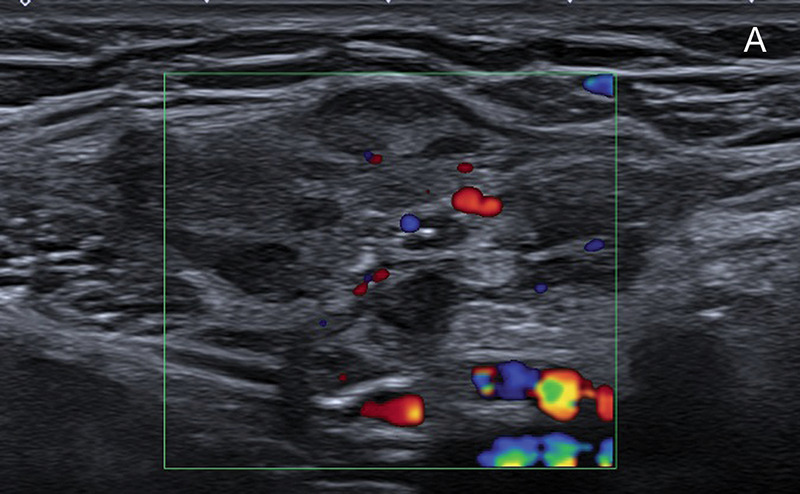

教学要点:磁共振成像(MRI)在诊断子宫内膜异位症中的作用越来越大,要求放射科医生熟悉深浸润性子宫内膜异位症的典型和非典型表现。

Teaching point: The role of magnetic resonance imaging (MRI) in diagnosing endometriosis is growing, requiring radiologists to become familiar with both typical and atypical presentations of deep infiltrating endometriosis.